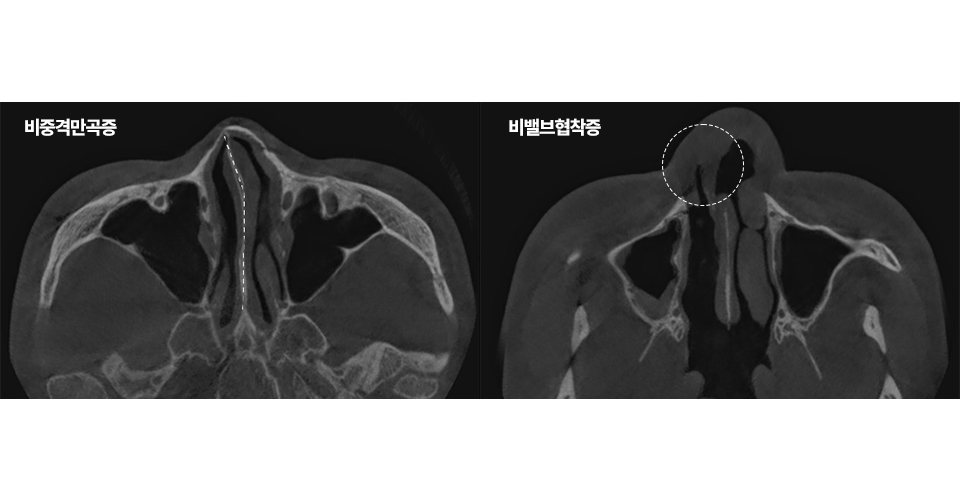

비밸브협착증과 비염차이, 약을 먹어도 코막힘이 안 낫는 이유코막힘이 오래 지속되면 대부분 비염 때문인가, 하고 생각...